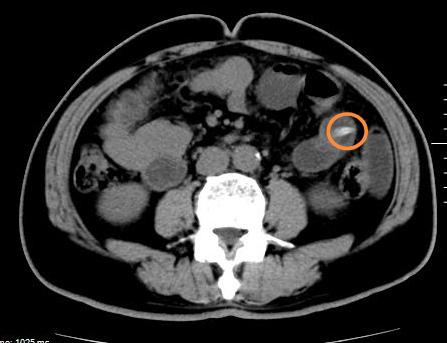

日前,66歲的戴先生,突發(fā)左側(cè)腹痛,并且癥狀越來越重。10個小時后,戴先生來到市人民醫(yī)院就診。普外四科(急重癥外科)收治了戴先生,醫(yī)生檢查戴先生已有腹膜體征炎,CT(圖1)見左腹內(nèi)可疑異物,并疑似刺穿腸管。

普外四科(急重癥外科)立即聯(lián)系手術(shù)室,為戴先生安排了急診手術(shù)。手術(shù)證實(shí)了術(shù)前診斷,一枚尖尖的棗核正穿腸而出(圖2),周邊腸管已布滿了膿苔,腹腔積聚大量膿液。